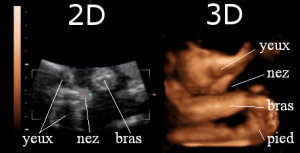

Figure 3 : Echographies 2D (à gauche) et 3D (à droite)

Sur l’échographie 2D de la Figure 3, les membres n’apparaissent pas de manière entièrement visible. Plusieurs images sont nécessaires afin de mieux les analyser et de comprendre les différentes activités du fœtus. À droite, par contre, sur l’échographie 3D, on remarque que le bras, la jambe et les détails du visage (yeux, nez, bouche, oreilles) sont beaucoup plus facilement distinguables. Les articulations également peuvent être repérées sans difficulté. Enfin, grâce à la 3D, certaines malformations cardiaques peuvent être plus rapidement détectées.